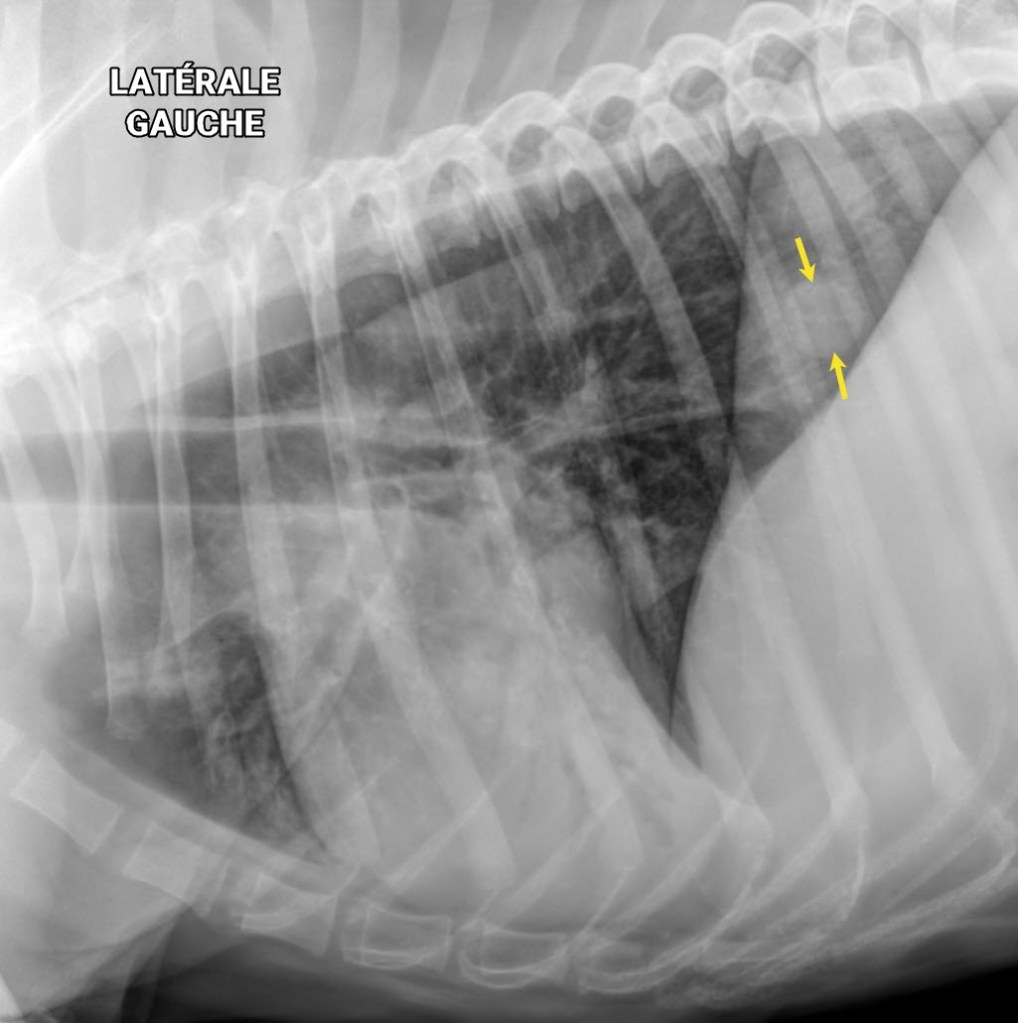

Ce chien boxer croisé de 12 ans mâle castré avait été présenté pour toux, vomissements et bruits respiratoires augmentés à l’examen. En plus de la pathologie alvéolaire ventrale signalant une bronchopneumonie, un nodule pulmonaire caudo-dorsal était suspecté sur les vues latérales (flèches jaunes), mais n’était pas bien visible sur la VD soumise à ce moment.

Lors du suivi radiographique de la bronchopneumonie, une DV a été effectuée et a permis de confirmer le nodule pulmonaire au lobe caudal droit.